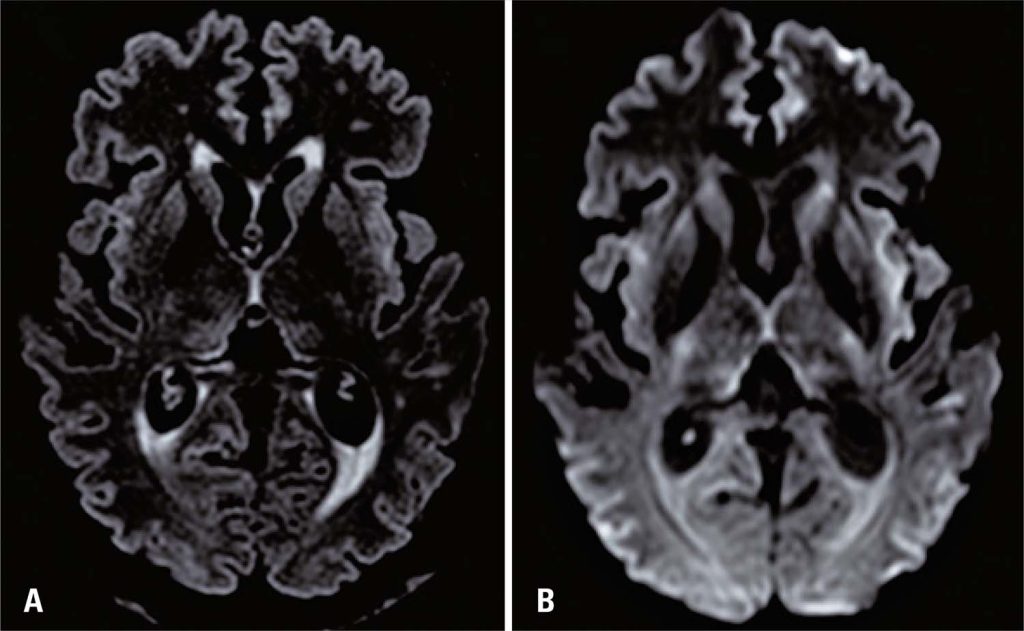

This study reports the case of a previously healthy 37-year-old woman who developed acute liver failure and hepatic encephalopathy (international normalized ratio 3.5, total bilirubin 30.2mg/dL, direct bilirubin 15.5mg/dL, aspartate aminotransferase 423U/L, and alanine aminotransferase 459U/L) after consuming an herbal medicine ( Citrus sinensis ) for lose weight. The patient went to the hospital due to jaundice and malaise, being hospitalized for evaluation. She underwent brain magnetic resonance imaging (MRI) due to lethargy, revealing cortical ribbon sign in diffusion-weighted and fluid-attenuated inversion recovery (FLAIR) sequences and hypersignal in the caudate nuclei, putamen, and insula bilaterally ( ). The cortical ribbon sign is a typical finding in patients with Creutzfeldt–Jakob disease; however, it has also been reported in patients with infection, hypoxia, electrolyte derangements, and hepatic encephalopathy (as in the present case). ( , ) Moreover, magnetic resonance spectroscopy revealed an increase in glutamate/glutamine, typically observed in hepatic encephalopathy ( ). Owing to the severity of the condition, the patient underwent liver transplantation and is improving progressively.